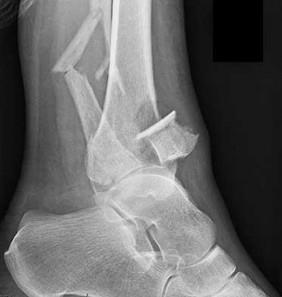

A 45-year-old female sustains a knee injury following a motor vehicle collision. Assuming the representative image demonstrates a medial tibial plateau fracture with articular depression (Schatzker IV), what is the most likely mechanism of injury?

A Schatzker IV fracture involves the medial tibial plateau. The medial plateau is structurally denser and stronger than the lateral plateau, meaning fractures here typically require higher energy. The classic mechanism is a varus force combined with an axial load. In contrast, lateral plateau fractures (Schatzker I-III) are typically caused by a valgus force with an axial load. High-energy trauma to the medial plateau is also highly associated with injury to the peroneal nerve, popliteal artery, and ligamentous structures (like the ACL or LCL).